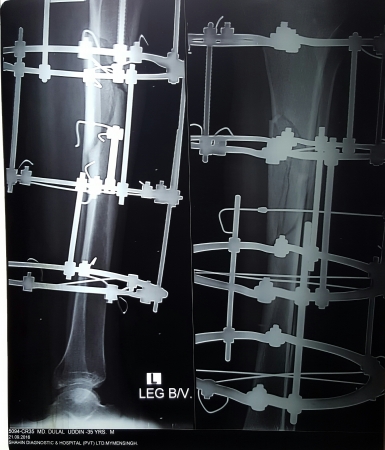

ইলিজারভ চিকিৎসা কি?

রাশিয়ায় ১৯৫০ সালে আবিষ্কৃত ইলিজারভ অর্থোপেডিক্স শাস্ত্রের একটি চিকিৎসা পদ্ধতি।

প্রতিদিন ১ মিঃ মিঃ করে হাড় লম্বা করা যায়।১৮-২০ সেমি পর্যন্ত (২০০৭ সাল), ২৭.৫ সেমি (২০১৬ সাল) হাড় লম্বা করা হয়েছে।

ইলিজারভ রিং/ ফ্রেইমটা কি?

এটি তৈরী হয় বিভিন্ন সাইজের ষ্টেইনলেস ষ্টিলের রিং, তার, রড-বোল্ট ও নাটের সংমিশ্রণে। ফ্রেইম গুলো নিখুতভাবে আকৃতি বিন্যাস করা হয় আলাদা আলাদা প্রয়োজন ও চাহিদা অনুযায়ী।

এই পদ্ধতিতে হাড় ধীরে ধীরে টানার ফলে রক্ত চলাচল বৃদ্ধি হয়ে নতুন হাড় তৈরি হয়। (Compression-distraction osteogenesis)

১) হাড় ভাঙ্গার চিকিৎসা (Treat fracture specially complex/open fracture)

২) জন্মগত/আঘাত জনিত বিকলাঙ্গতা রোগ সারানো/বাঁকা হাত-পা সোজা করা (Reshape/Correct deformities)

৩) প্রয়োজনমত হাত-পা লম্বা/ছোট হাড় বড় করা (Bone as well as Limb Lengthening )

৪) যে হাড় আদৌ জোড়া লাগানো সম্ভব নয় অন্য কোন পদ্ধতিতে সে হাড় জোড়া লাগানো সম্ভব এই পদ্ধতিতে (Non-Union, Pseudoarthrosis)

৫) হাত-পায়ের ইনফেকশন জনিত যেকোন রোগের চিকিৎসা যেমনঃ অস্টিও মাইয়েলাইটিসের চিকিৎসা, Infected Non-Union-INU etc